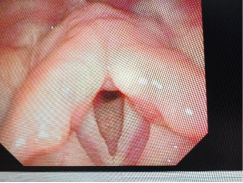

双侧声带小结

2. 喉镜检查

使用喉镜(光学仪器),医生可以直接观察声带,确认是否存在小结及其大小和位置。这是确诊的重要方法。